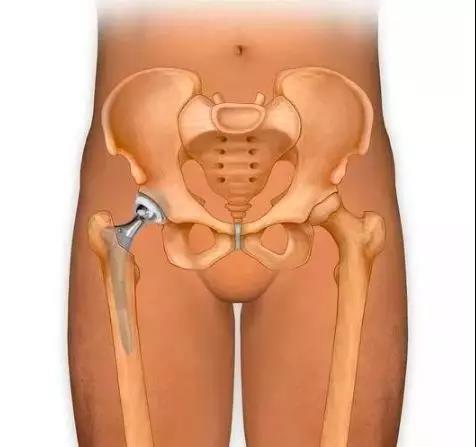

髋关节翻修术是指通过重新植入能够牢固固定的新假体及恢复(或基本恢复)关节的解剖形态而恢复关节功能。随着人工全髋关节置换术(THA)的广泛开展,由于无菌性松动、骨溶解、感染、骨折假体失效、位置不佳、脱位等原因而致的疼痛及关节功能障碍日益增多,因而髋关节翻修术的绝对数量也在增加。但翻修术较初次置换而言花费高、技术复杂、对手术技巧和临床经验要求较高,因而显得越来越重要。

邱华耀主任介绍说,随着医学发展,人工关节置换开展越来越广泛,现在的假体使用寿命也越来越长。但以往人工关节平均寿命15~20年左右,由于假体的磨损,将会出现关节松动、下沉、磨损及假体周围骨溶解等问题,导致关节疼痛,直接影响正常的工作和生活。关节翻修手术可以有效改善和缓解病人痛苦,提高生活质量。对于已接受人工假体置换的患者,平时要做好以下三点来保护自己的人工关节: